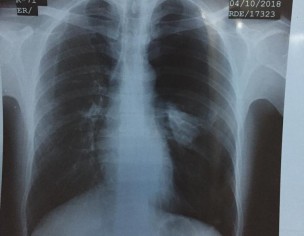

I have Pain in Left side Chest. My ECG report and Chest X Ray is attached. Kindly advice me what actual problem

x ray showing left sided opacity,should be investigated,unable to comment without examining patient.

dear i would like you to have these tests done. HRCT chest, D-dimers

your Chest Xray has left sided opacity. you need to be checked by pulmonologist who may advise further investigations in order to reach the diagnosis.